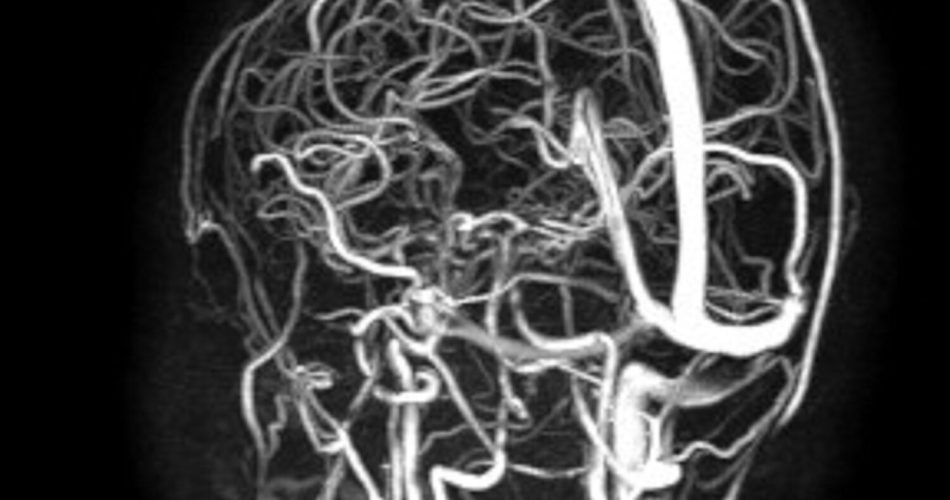

angioRM pre - trombosi asse trasverso-sigmoide.giugulare dx

La minore era giunta al Pronto soccorso pediatrico con un grave offuscamento visivo e una paralisi dei muscoli oculari. Gli accertamenti diagnostici avevano evidenziato una mastoidite all’orecchio destro complicata da una trombosi venosa cerebrale estesa fino al seno cavernoso, una condizione che comportava un elevato rischio di perdita irreversibile della vista.

Il controllo a sei mesi ha confermato la quasi totale risoluzione della trombosi e il pieno recupero della funzione visiva, senza esiti neurologici residui. Il direttore generale del Policlinico, Antonio Sanguedolce, ha sottolineato che nel corso del 2025 sono state effettuate oltre 70 procedure neurochirurgiche pediatriche, molte delle quali su pazienti affetti da tumori cerebrali, evidenziando come l’approccio multidisciplinare rappresenti un elemento centrale nella gestione dei casi più complessi anche in età pediatrica.